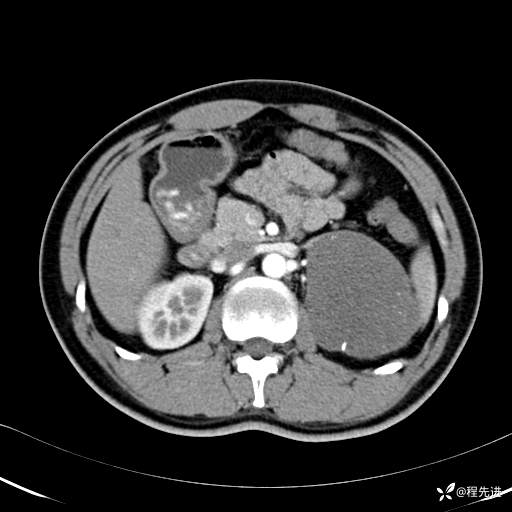

【腹盆】特别精彩病例|体检发现的左侧腹膜后占位期待您的精彩解读

患者年龄:25岁

简要病史:体检发现

CT平扫:(CT值:平扫,27HU,动脉期,27HU,门静脉期,31HU,平衡期,32HU)

CT增强:

冠状位重建: